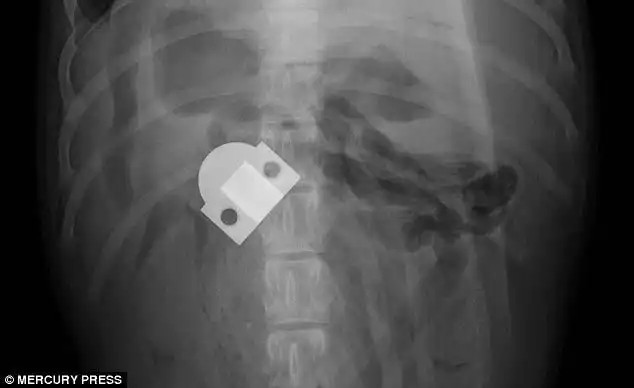

6-месячный лабрадор-ретривер Эвери, который съел шарнир от двери